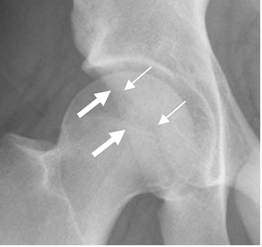

Se deben determinar los bordes anterior y posterior de la cavidad acetabular. Normalmente la pared anterior no se superpone a la posterior, antes del borde lateral. (4). (Fig 12).Si la cruza, origina el signo de cruce positivo e indica sobrecubrimiento posterior o anteversión acetabular. (4).

Fig 12. Cavidad acetabular.

Rx AP. Reborde anterior (Flecha delgada) y reborde posterior (Flecha gruesa).